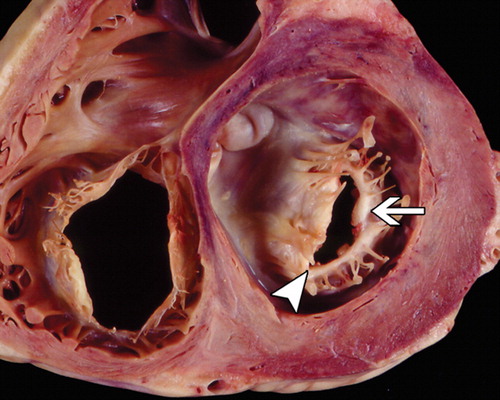

پس از بهبودی بیماری اولیه التهاب و زخم ایجاد شده بر روی دریچه های قلب و به ویژه دریچه میترال موجب فیبروز ، ضخیم شدن و بهم چسبیدن اعضای دریچه ها به یکدیگر می شود. در دریچه میترال لت های دریچه از کناره ها به هم متصل می شوند و هم چنین لبه لتهای دریچه ضخیم شده و کلسیم در آنها رسوب می کند. در مراحل پیشرفته بیماری حتی ناحیه کورد و طناب های زیر دریچه هم ضخیم شده و به هم متصل می گردند.